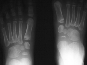

RADIOGRAPHS : AP, lateral and oblique views bilateral feet demonstrate

bilateral avascular necrosis of the navicular.

RADIOGRAPHIC FINDINGS

- flattening of the navicular

- narrowing of the navicular AP diameter in the lateral view

- irregular rarefaction and sclerosis

- irregular ossification of the navicular is seen in normal feet

- diagnosis of Kohler's disease should only be made when symptoms are

present